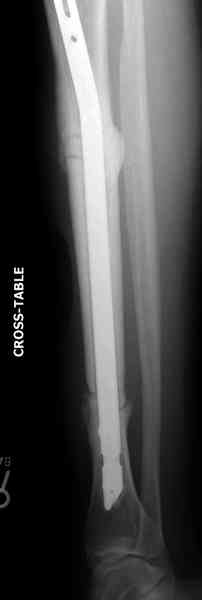

Оперирован в военном госпитале с заменой сегмента

аллокостью большеберцовой кости и после демобилизации явился для постоянного наблюдения по месту жительства.

Наши имели проблему со сращением, пришлось им сделать динамизацию, дополнительную аутопластику.

Снимки представлены.